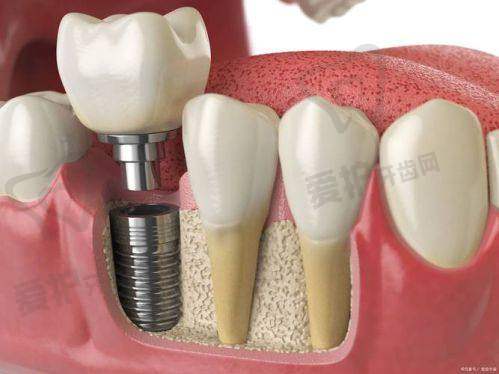

高品质的材料:美国皓圣种植体采用了优质的钛材料,这种材料具有良好的生物相容性,能够与人体牙槽骨紧密结合,形成稳定的骨结合,为种植牙的长期使用提供了保护。

独特的设计:其种植体的表面经过特殊处理,具有良好的亲水性,能够促进种植体与牙槽骨之间的血循环,加快骨结合的速度,缩短种植周期。同时,种植体的螺纹设计合理,能够增加与牙槽骨的接触面积,提高种植体的稳定性。